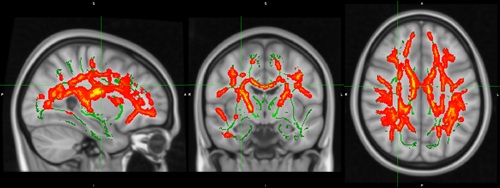

Imatges de ressonància magnètica cerebral que mostren les àrees de la matèria blanca on els canvis en inflamació cerebral associats al tractament antipsicòtic varien segons el consum previ de cànnabis

El treball ha analitzat imatges de ressonàncies magnètiques cerebrals d'un centenar de persones, tant pacients que havien patit un primer episodi psicòtic com voluntaris sans, mitjançant una nova tècnica que mesura l'aigua lliure extracel·lular. És el primer estudi que fa servir aquesta tècnica per estudiar l'efecte del consum de cànnabis en psicosi.

A l'estudi hi han participat 62 pacients diagnosticats de forma recent i 38 controls. I els resultats del treball mostren diferències en la inflamació cerebral entre les persones que pateixen un primer episodi psicòtic en funció de si consumeixen cànnabis o no. Diferències que també es veuen en les persones que no tenen psicosi, encara que consumeixin. Un fet que, segons el Dr. Daniel Bergé, psiquiatre de l'Hospital del Mar i membre del Grup de Recerca en Neuroimatge en Trastorns Mentals de l'Hospital del Mar Research Institute, "suggereix una associació entre l'ús de cànnabis i alteracions en el sistema inflamatori en els primers episodis psicòtics". A la vegada, els resultats obtinguts indiquen que el cànnabis pot influir en la capacitat dels tractaments contra la psicosi de reduir aquesta inflamació. En aquest sentit, "la potencial associació del consum d'aquesta substància amb l'alteració de la reducció de la inflamació cerebral assolida gràcies als tractaments antipsicòtics ens ofereix una visió d'un dels possibles factors que influeixen en el baix èxit del tractament en aquests pacients", afegeix el Dr. Bergé.